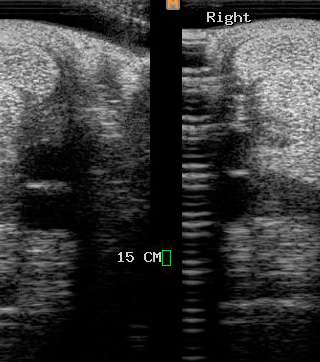

Ecografía

Cuenta con Ecografía digital de alta complejidad.

17 años de experiencia siendo una de las ecografistas más reconocidas en la práctica de equinos. Realiza pasantías en la universidad de Davis California y en Mid-Atlantic Equine Medical Center en New Jersey.